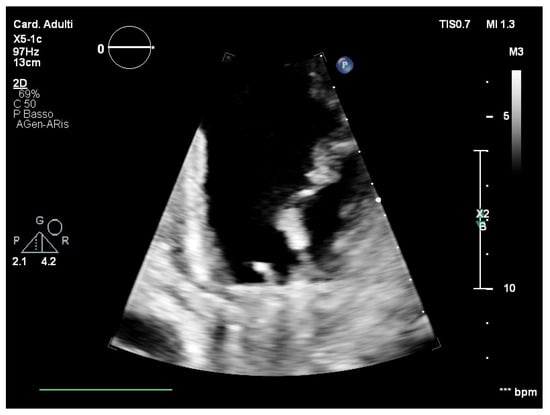

2. Case Report